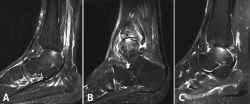

Otras clasificaciones están basadas en la tomografía axial computarizada (TAC) o en la resonancia magnética (RM) y engloban las LOC tanto agudas como crónicas. El estudio mediante TAC permite más precisión para definir el tamaño y la localización de las lesiones, así como de la presencia de cambios quísticos. Ferkel y Sgaglione desarrollaron un sistema de clasificación basado en la TAC (Figura 2), que tiene la particularidad de servir de apoyo para la planificación preoperatoria y la elección del tipo de tratamiento más adecuado (tornillo/pin, microfractura o injerto)(18).

Figura 2. Imágenes de resonancia magnética que muestran diferentes fases de lesión osteocondral. A: estadio IIA, que muestra edema óseo circundante; B: fractura osteocondral en estadio IV con un fragmento desprendido y desplazado; C: estadio V que muestra la formación de quistes subcondrales.

Hepple desarrolló un sistema de clasificación basado en la RM y que también tiene implicaciones de indicación (Tabla 2). Actualmente, la RM constituye el mejor método para evaluar la estabilidad de un fragmento mínimamente o no desplazado, lo que puede influir en la necesidad, o no, de practicar su fijación (Figura 3)(19,20).

Figura 3. Imagen de tomografía axial computarizada de un estadio III que muestra un fragmento no desplazado con lucencia por debajo.